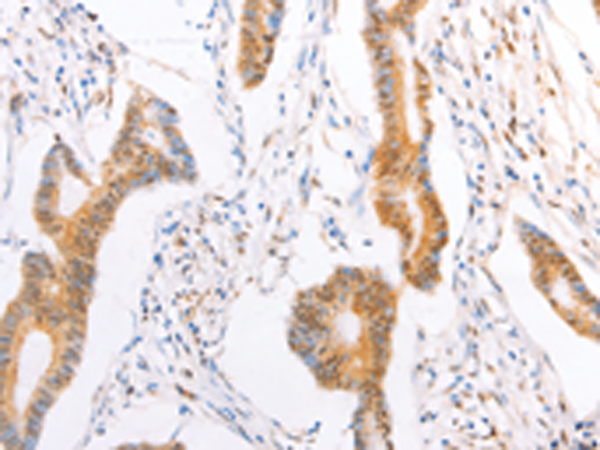

分类: 科研抗体货号: P07679别名: RNF84; MGC:39780应用: IHC反应种属: Human, Mouse